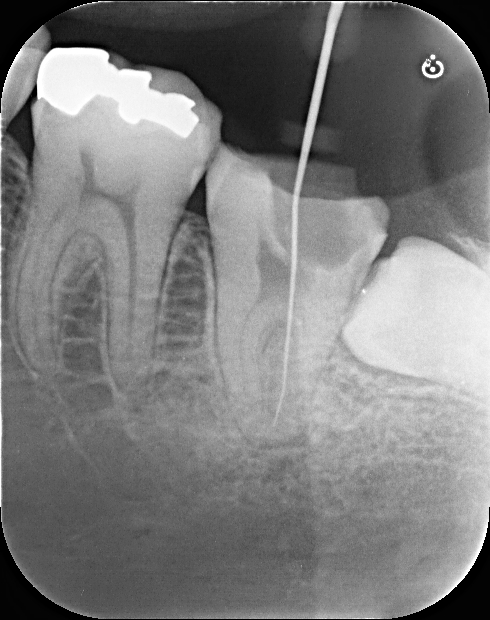

初診時のレントゲン写真です。

画面向かって一番右下の歯(親知らずの1つ手前です)が虫歯で黒くレントゲンに映っています。

それで上記のレントゲン写真を撮影しました。

歯の真ん中で歯が割れている((+_+))

しかも、かなり大きく損傷しており、今回は修復困難と判断しました。(穴の大きさによっては修復可能な場合もあります。)

レントゲン写真で、画面向かって左下1番奥に横向きに生えた親知らずが今回は存在しました。CT精密検査を行った所、移植の条件に当てはまることが判明し、移植治療を行うこととなったのです。以下に術後のレントゲン写真を示します。

【移植後のレントゲン写真】

保存困難な歯を抜歯し、奥の親知らずは歯茎の下の完全に埋まっておりましたが、このように移植を行い、手術は30分ほどで処置終了しております(^^)/